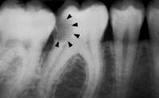

Sistema radiográfico ICDAS

(Radiografía Bite-Wing) |

R0 |

No hay

radiolucidez |

Estadios

iniciales * |

|

RA1 |

Radiolucidez en

1/2 externa del esmalte |

RA2 |

Radiolucidez

en la 1/2 interna del esmalte ± UAD

(Unión amelo-dentinaria) |

Se lo considera aún un estadio

inicial porque no hay dentina

infectada ) |

RA3 |

limitada al 1/3 externo de la

dentina |

Estadio

moderado

(En este estadió

comiemza la infección de la dentina por bacterias orales) |

RB4 |

Radiolucidez que

alcanza hasta el 1/3 medio de la

severos

(Infección franca de la dentina) |

RC5 |

alcanza hasta el 1/3 interno de la

dentina, clínicamente cavitada

RC6 |

la pulpa, clínicamente cavitada

*

Nota- La

mayoría de lesiones confinadas al esmalte no

se ven en las radiografías.

Tabla 4: Clasificación

radiográfica ICDAS

Radiografía de aleta mordible

(Bite-Wing)